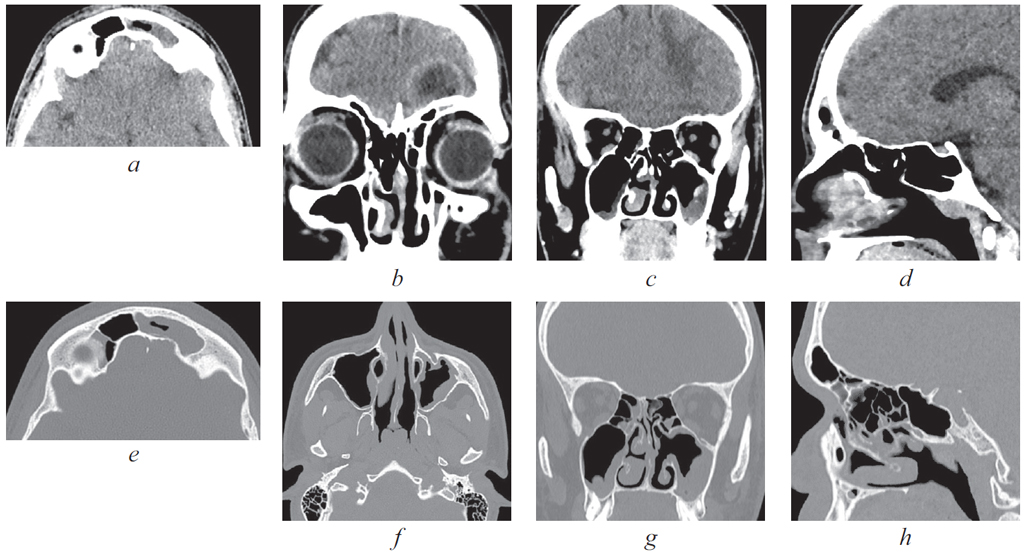

Риногенные внутричерепные осложнения, такие как абсцесс головного мозга и тромбоз вен и синусов головного мозга, по сей день остаются грозной, жизнеугрожающей патологией, не редко заканчивающейся летальным исходом, несмотря на широкое развитие антибактериальной терапии и приверженность пациентов к проводимому лечению. Нередко причиной развития внутричерепных осложнений служит обострение хронического воспалительного процесса в придаточных пазухах носа, тогда как острая ЛОР-патология синусов приводит к развитию риногенных осложнений лишь в небольшом проценте случаев. К сожалению, высокое развитие лучевой и лабораторной диагностики не всегда позволяет вовремя диагностировать данные состояния и оказать адекватную хирургическую помощь. В детском и подростковом возрасте важно выполнить своевременное полное и в то же время малоинвазивное, не приводящее к инвалидизации, хирургическое пособие. Анализ зарубежной литературы последних лет показывает, что нейрохирургические операции в различном объеме (от трепанопункции головного мозга до краниотомии) встречаются в подавляющем большинстве случаев лечения риногенных внутричерепных осложнений. В статье приводятся два клинических случая успешно пролеченных в отделении оториноларингологии Санкт-Петербургского государственного педиатрического медицинского университета пациентов с внутричерепными осложнениями без высокотравматичной нейрохирургической операции. Комбинация эндоназальной эндоскопической операции и массивной адекватной консервативной терапии (антибиотикотерапия в сочетании с применением антикоагулянтов при синус-тромбозе) позволяет добиться выздоровления пациента без обращения к нейрохирургическому вмешательству.